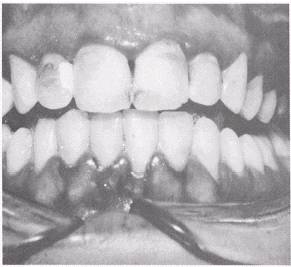

PERIODONTITIS

Periodontitis (fig. 5-9) is a chronic inflammatory condition that involves the gingiva, crest of the alveolar bone, and periodontal membrane. This condition results in loss of bone that supports the teeth, periodontal pocket formation, and tooth mobility. It usually develops as a result of untreated chronic marginal gingivitis. The color of the gingival tissues is intensified and becomes bluish red as the disease progresses. A gradual recession of the periodontal tissue will occur. Neglected deposits of calculus and formation of additional calculus over time contribute to the spread of the disease. Like marginal gingivitis, it may affect the entire dentition, or only localized areas.

Figure 5-9.\Periodontitis.